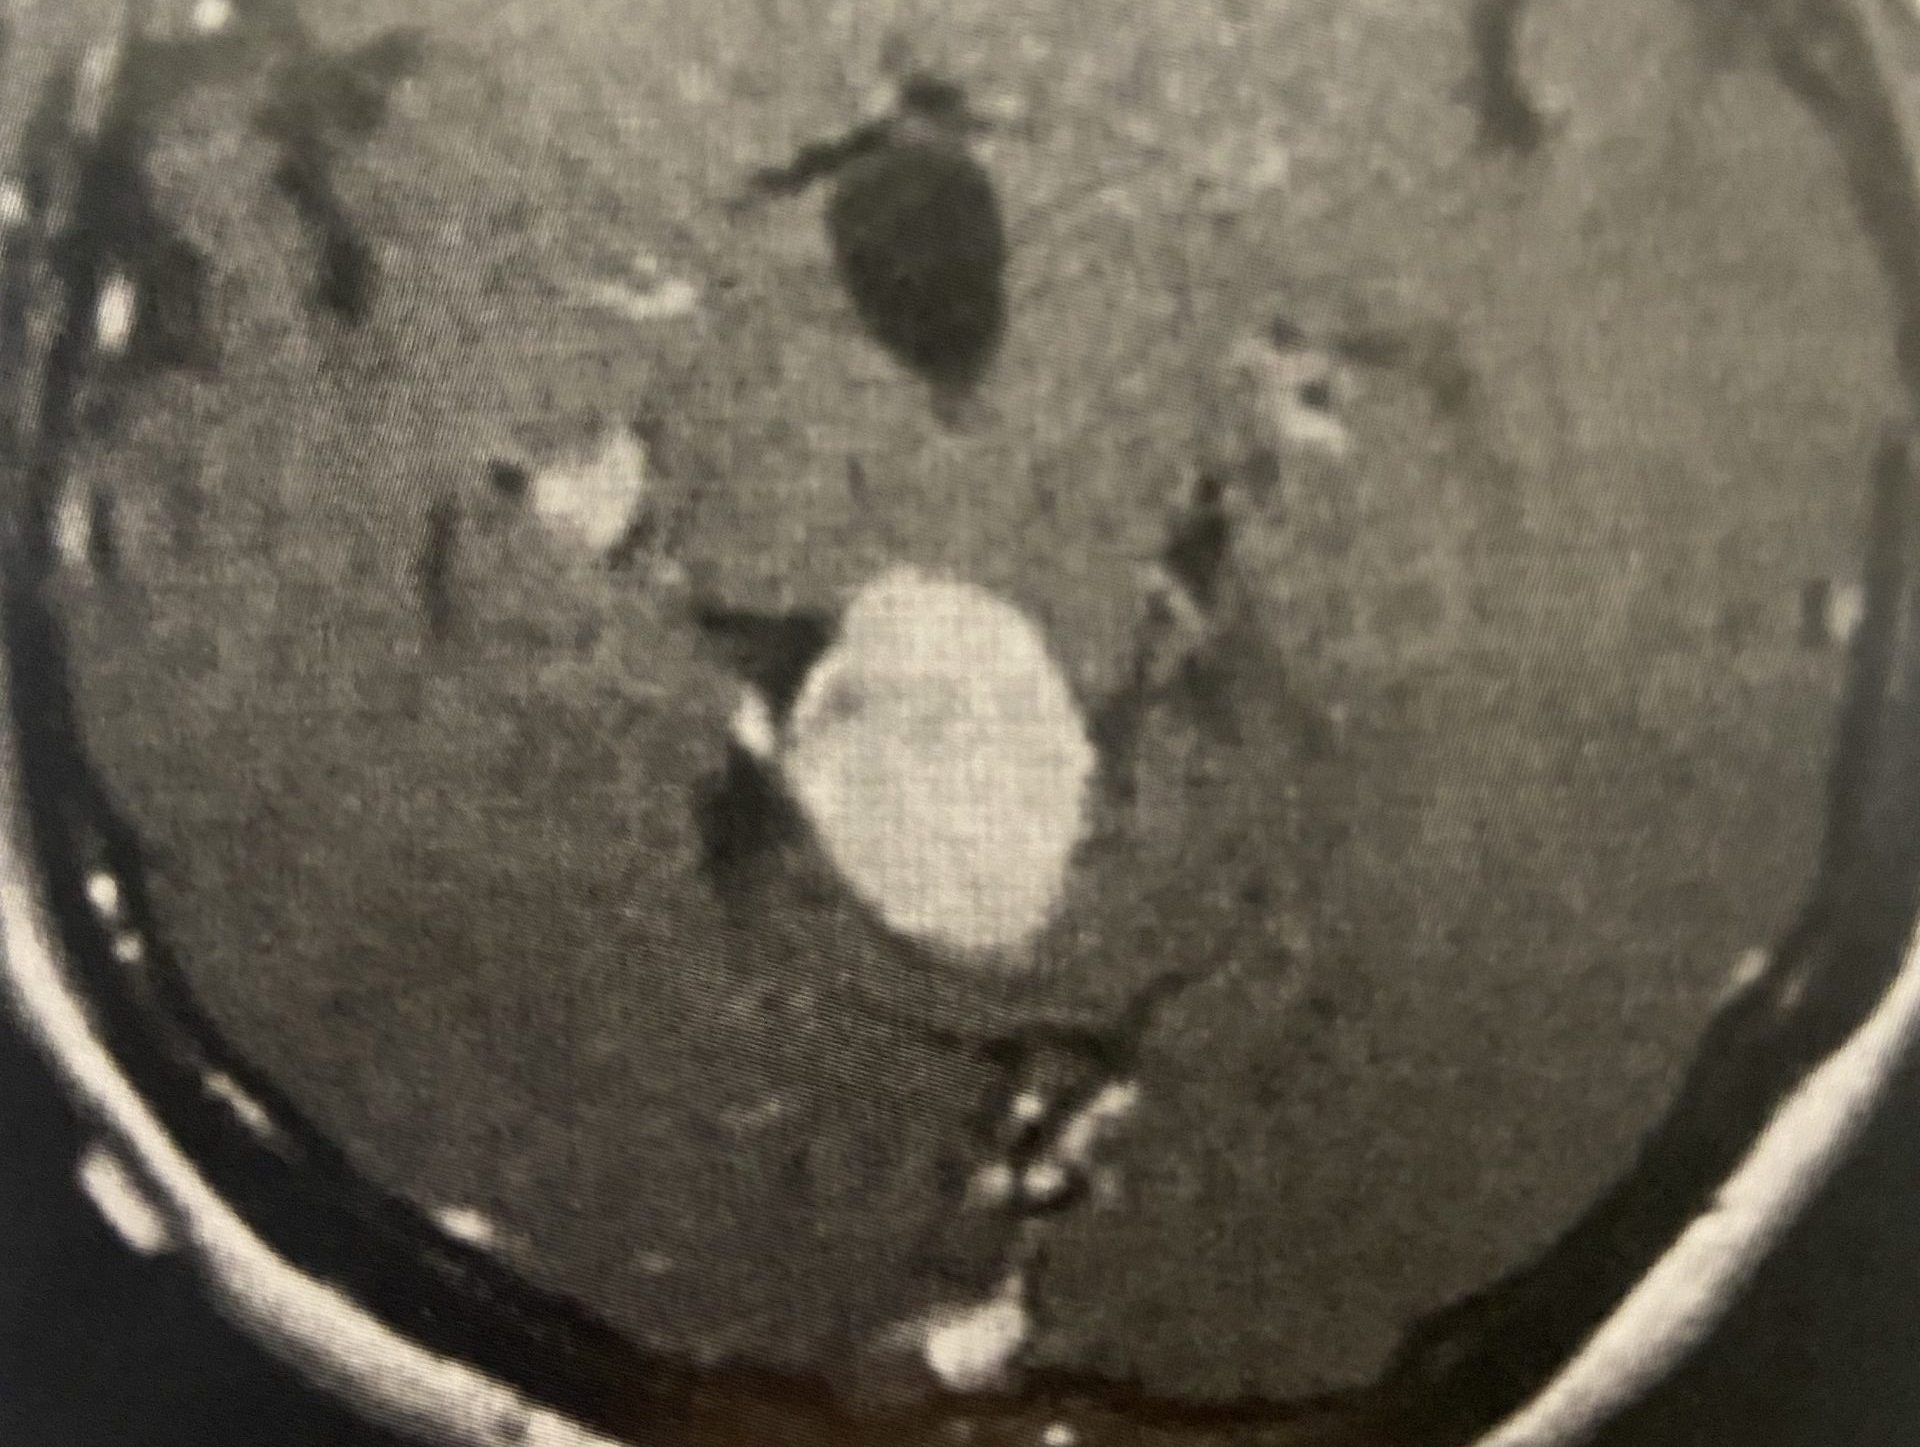

This is a 39 year old physician with a long history of sinus issues, who more recently had noted an increased drainage of clear fluid from his nose. Testing of the fluid for Beta-2-transferrin demonstrated that it was consistent with cerebrospinal fluid (csf). MRI and CT scan demonstrated an encephalocele in the frontal most part of the anterior skull base, on the left, just off midline (Figures 1a,1b,1c). For the last 3 weeks, he has also been having headaches and neck pain.

The patient was sent to the hospital. He was noted to be afebrile with a normal white blood cell count. Nonetheless, to be safe, he was started on broad spectrum antibiotics. Two days later he was brought to the operating room and underwent a left frontal craniotomy to repair the encephalocele. Brainlab neuronavigation was used to avoid violating the frontal sinus, and a lumber drain was used to give adequate brain relaxation. A sizeable defect was noted in the skull base. Brain tissue was amputated from beneath the defect, and the defect was repaired with allograft.

Encephaloceles are defects in which the brain exits the skull through defects in the skull. They are usually discovered at birth, and usually present as obvious protrusions from the head. However, it is possible to have an encephalocele present during adulthood, as in this case. The skull defect through which the brain protruded was from the anterior skull base into the ethmoid sinus, so it would not have been grossly noticeable. It is unclear whether some of this patient’s chronic sinus issues may have been secondary to this encephalocele, or may have ultimately led it to tear, and start leaking csf from the nose. Regardless, in light of the csf rhinorrhea, surgery was indicated to repair the defect to stop the csf leak and prevent the development of meningitis or brain abscess.